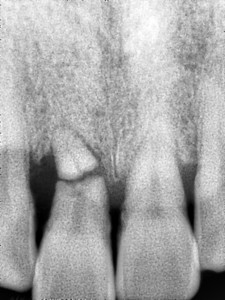

김정아 앞니 치료전 PA

작은 방사선 사진을 하나 찍어 보았습니다.

오른쪽 위 중절치의 치아 뿌리 끝에 수평으로 금이 가 있는 것을 볼 수 있습니다.

전반적으로 중절치 두 개가 동요도도 크고 치아 뿌리가 짧아 오래 쓰기는 힘들어 보입니다.

그래서 중절치 두 개를 발치하고 앞니 임플란트 를 식립하기로 결정하였습니다.